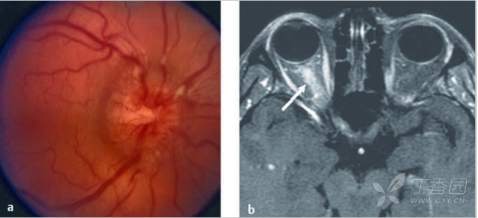

视神经乳头水肿,或称视盘水肿,是一个用来描述筛板前的局限性肿胀(图9.1)的非特异性术语。

图9.1 (a)右眼视神经肿胀。视盘边缘模糊,无中央视杯。(b)肿胀视神经的矢状切面